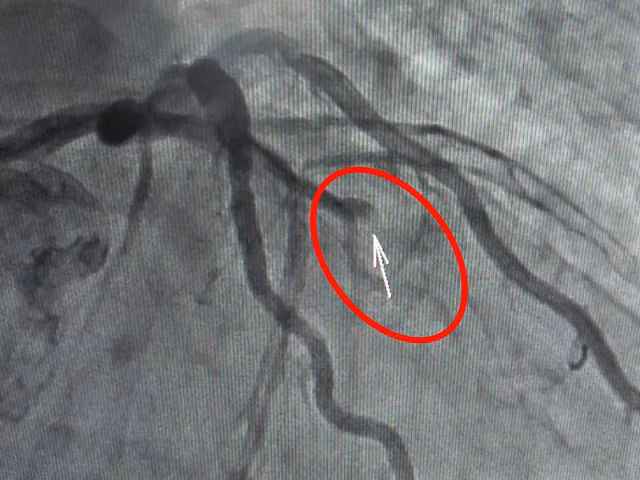

Hình ảnh chụp mạch vành cho thấy, bệnh nhân bị tắc hoàn toàn động mạch liên thất trước

Trong quá trình can thiệp, ê kíp ghi nhận bệnh nhân bị tắc hoàn toàn động mạch liên thất trước, hẹp kéo dài lan tỏa nhánh LAD từ sau nhánh vách. Bệnh nhân được đặt stent đoạn gần động mạch liên thất trước tái thông vị trí bị tắc.